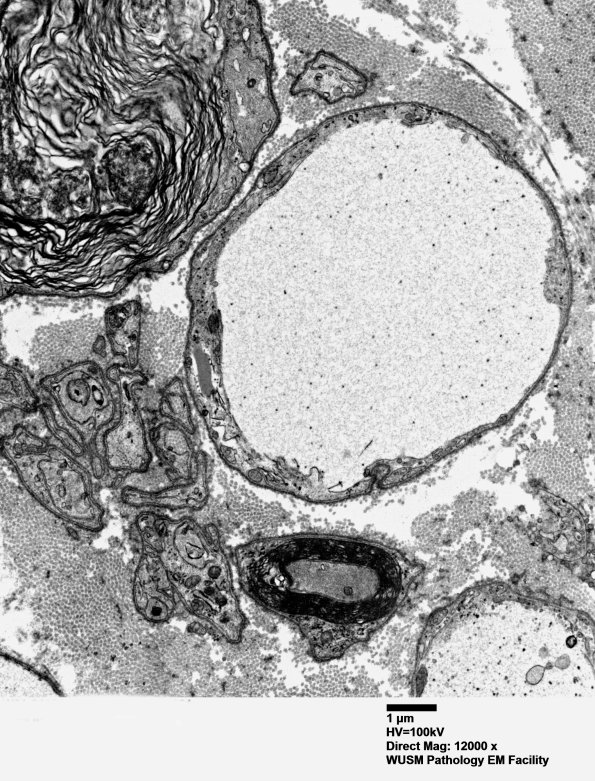

Ultrastructural examination shows that such artifactual “demyelinated axons” fail to have a sharp border with the Schwann cell cytoplasm and also fail to exhibit the cytoskeletal elements expected of an axon. (electron micrograph)